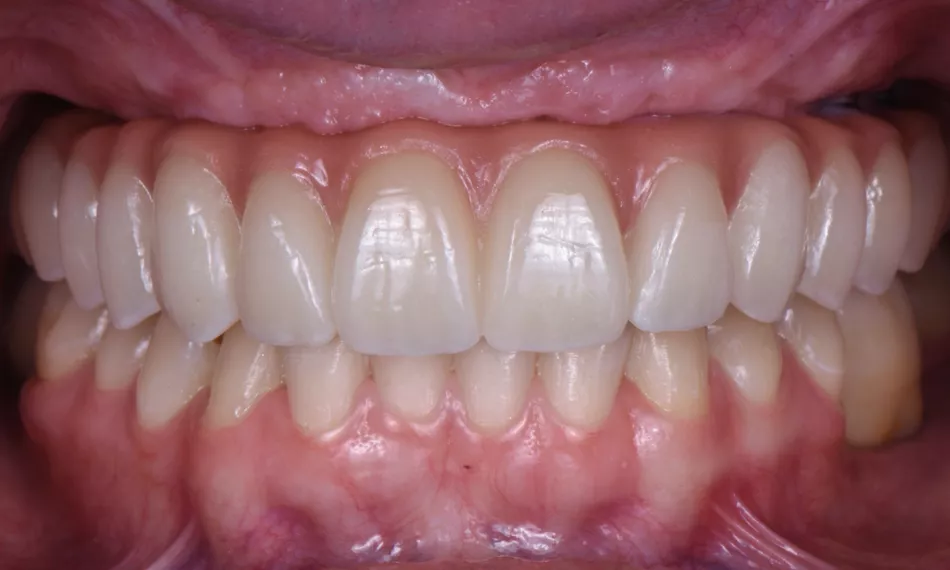

The final outcome of the treatment emphasizes the esthetic excellence of the zirconia monolithic prosthesis (Fig. 15), which blends seamlessly with the natural dentition. Its functional durability ensures long-term stability, providing both visual appeal and enhanced performance. This result has greatly improved the patient's overall satisfaction and quality of life.

Fig. 15

Additionally, lateral views taken at the end of the treatment offer a thorough perspective on the placement and fit of the prosthesis. These images confirm proper alignment with the surrounding tissues and occlusion, ensuring both functional performance and esthetic harmony, further contributing to the overall success of the treatment (Figs. 16,17).